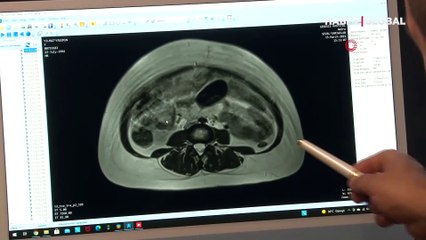

Geceleri yatarken vücudunun içerisinde hareketlilik olduğunu fark ederek doktora başvuran 27 yaşındaki Yasemin Yılmaz’ın karnından, neredeyse 9 aylık bebek boyutuna ulaşan 2 buçuk kilogramlık kist çıkarıldı.